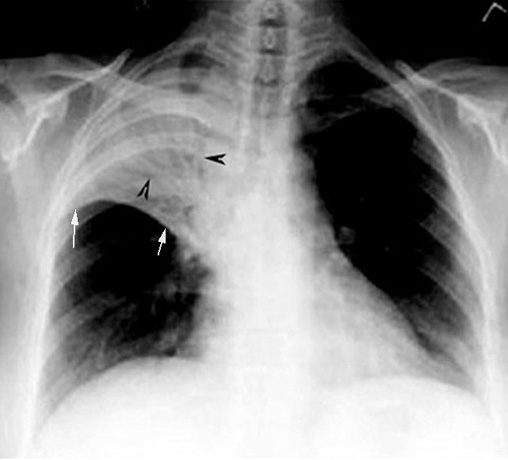

Lobar Pneumonia Cxr

Lobar Pneumonia Cxr : • afebrile • recurrent pneumonia in same location.